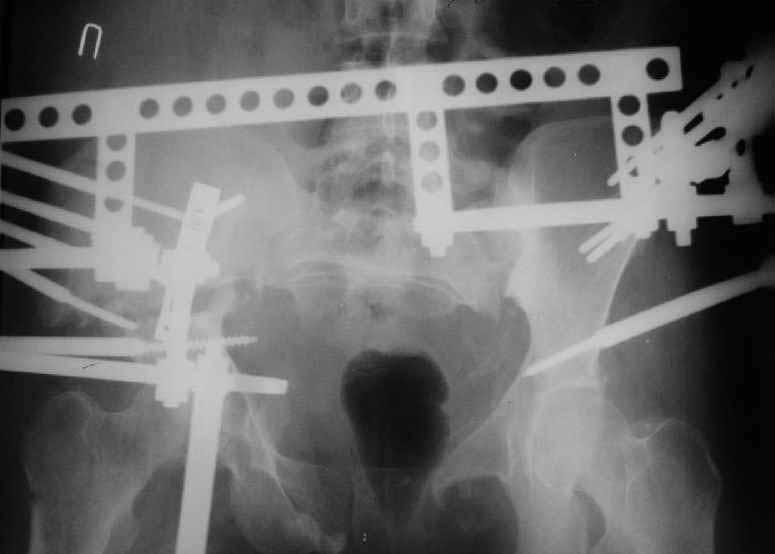

On Jan 26, 2005 the right wing was osteotomized, its segment with the

acetabulum was moved downwards, the ilium was plated, and pelvic external

fixator with femoral extension applied (left image).

After wound healing, anterior reconstruction was performed, iliosacral

screws inserted, the femoral frame removed.

To date wounds healed, the patient walks with crutches, no

weight-bearing at the right side (rest images).